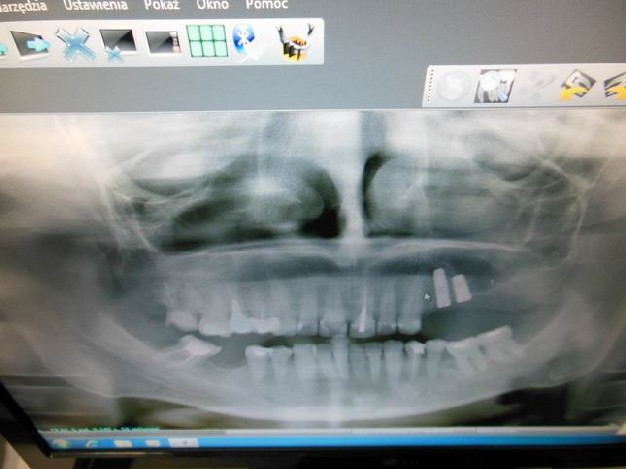

Ortodoncja CBCT

Leczenie chirurgiczno-ortodontyczne wad zębowych z zastosowaniem tomografii spiralnej CBCT w naszej klinice.